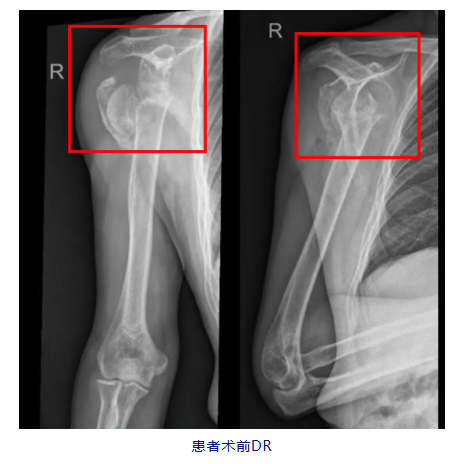

据悉,60岁的岑大叔在种玉米时不慎摔倒致右肩疼痛伴活动受限,在家人陪同下到当地医院就诊,经X线检查后提示:“右肩关节脱位伴肱骨外科颈粉碎性骨折”,由于当地医疗条件有限,又转至医科大一附院河池医院关节、运动医学科进一步治疗。

入院后,关节、运动医学科主任吴毅华主任医师为患者进行了专科查体,发现患者右方肩畸形,右肩峰前、外缘压痛,右肩关节主动、被动活动受限。经过影像学检查,被诊断为右侧肱骨头缺血性坏死、右侧陈旧性肱骨近端骨折、右陈旧性肩关节脱位等。“患者伤情非常严重,加上年纪也比较大,肩袖修复效果差,要最大程度恢复肩关节功能,就需要为患者进行右侧反向全肩关节置换手术治疗。”吴毅华说。